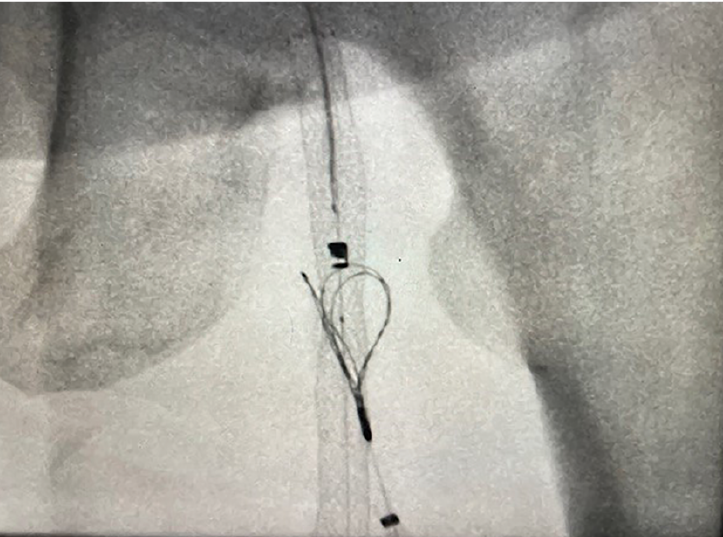

This interview with operator Bernardo Cortese, MD, walks through a complex, high-risk PCI that required rapid decision-making, close collaboration, and meticulous technique. The case report describes a critically ill 54-year-old man whose survival and recovery depended on rapid coordination, advanced imaging, and decisive action in the cath lab. The patient presented with acute dyspnea and atrial fibrillation with rapid ventricular response, quickly deteriorating into hemodynamic instability and cardiac arrest with pulseless electrical activity. After successful resuscitation, he was found to have severe left ventricular dysfunction and extensive coronary disease.